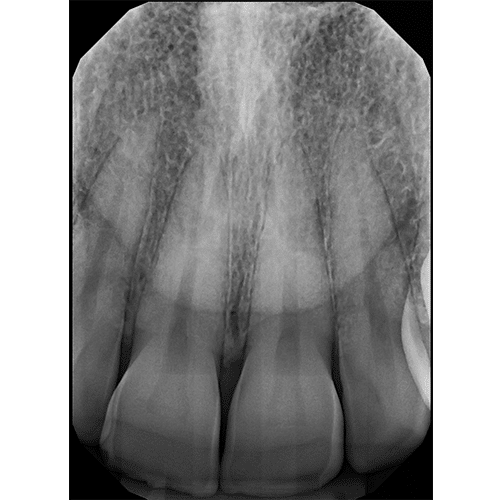

Diagnostic Quality You Can See

Digital X-Ray Sensor

Clio Prime

The elite digital x-ray sensor with EveryShot X-Ray Capture technology. Eliminates under and overexposure, works with any handheld or wall mount x-ray unit. Made in the USA.